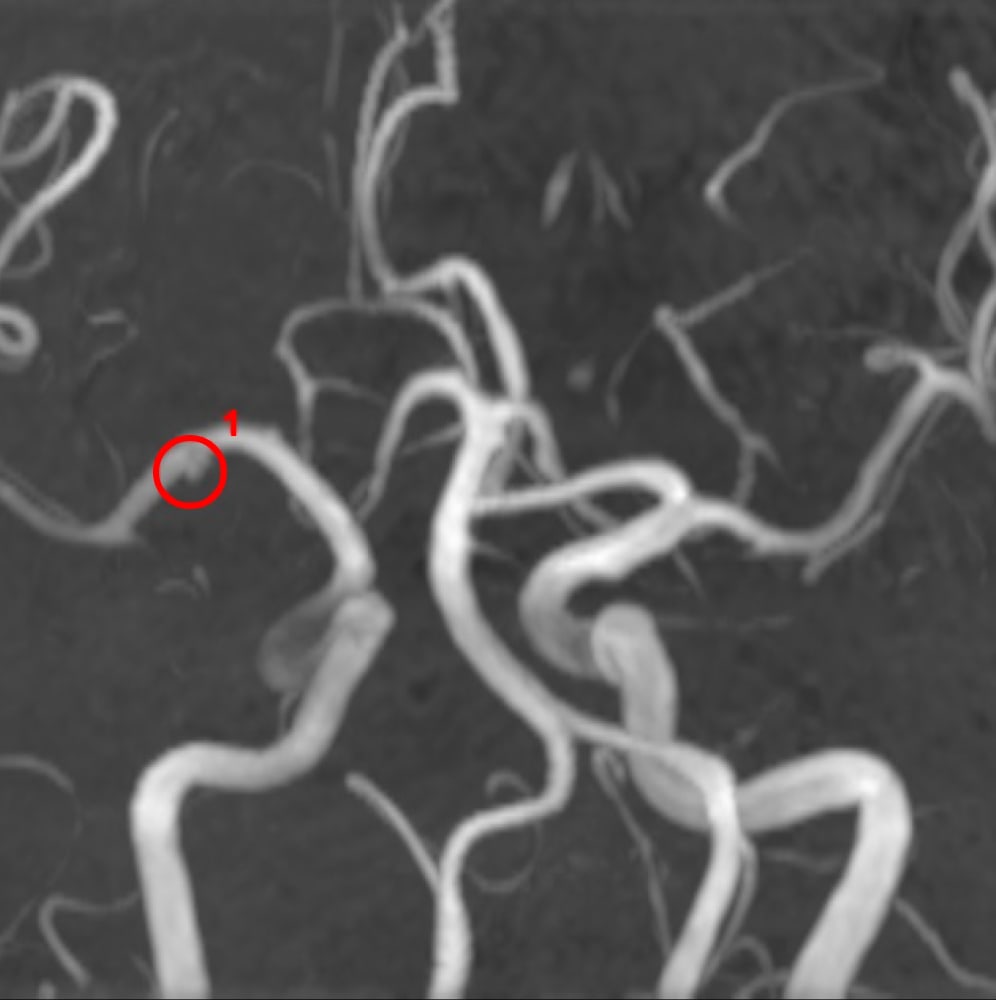

解析事例

中大脳動脈